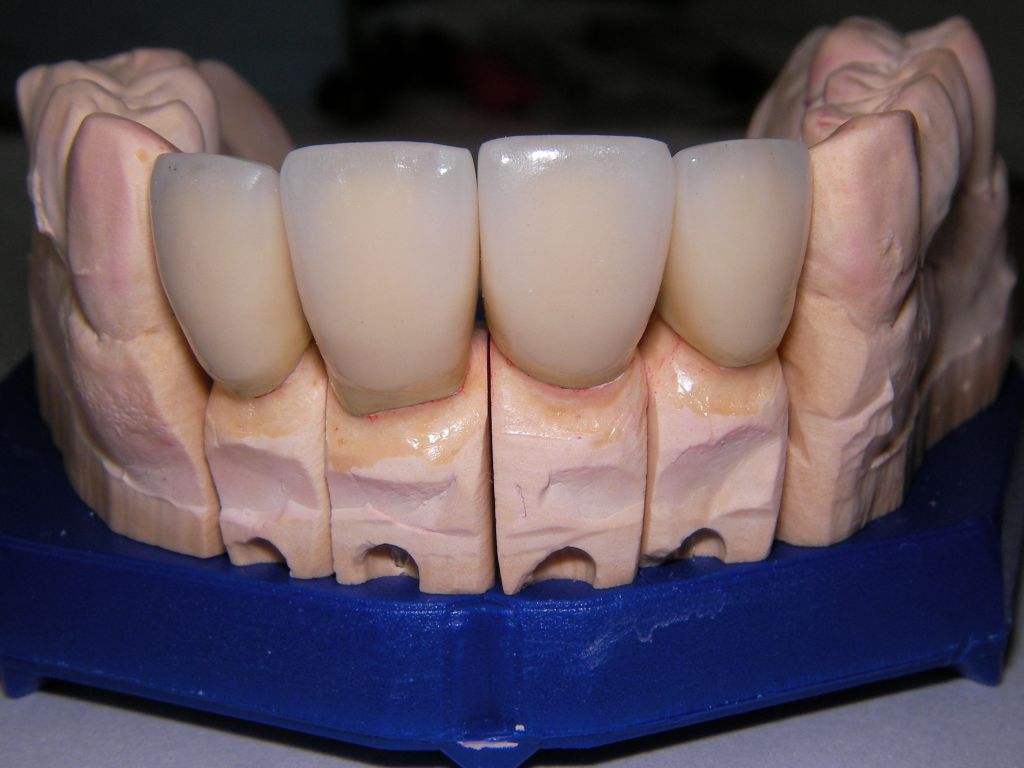

Links das Kontrollfoto nach der Sitzung am 17.2.06. Damit war die Vorbehandlung in diesem Fall abgeschlossen. Am 28.2.06 erfolgte die endgültige Präparation (das "Beschleifen") aller 4 Zähne. Links das Modell, auf dem die Kronen gefertigt worden waren. Rechts kurz vorm Zementieren der Kronen am 13.3.06. Aus der Längendifferenz der Zähne rechts und links kann man darauf schließen, daß die Präparation tief unter dem Zahnfleisch erfolgen mußte.

Links die Kronen aus dem Dentallabor "Heitmeyer Zahntechnik", Osnabrück. Man sieht praktisch keinen Metallrand. Der Patient war zur Farbbestimmung im Dentallabor - so halten wir es praktisch immer. Rechts das Ergebnis bei der 1. Nachkontrolle am 27.3.05. Das Zahnfleisch muß sich noch etwas erholen.